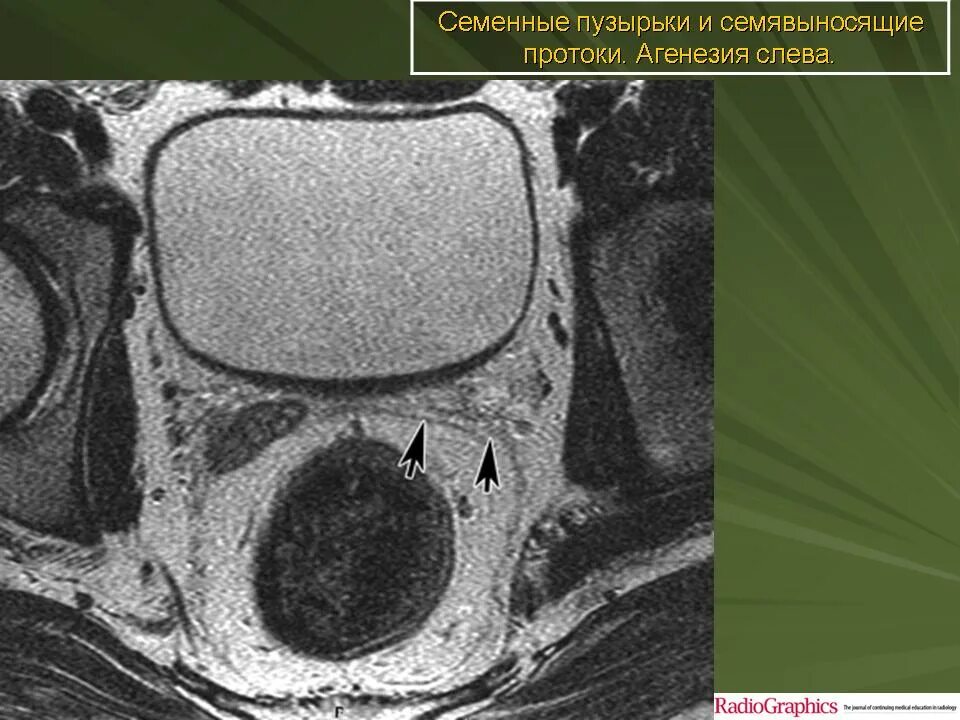

Мрт 8